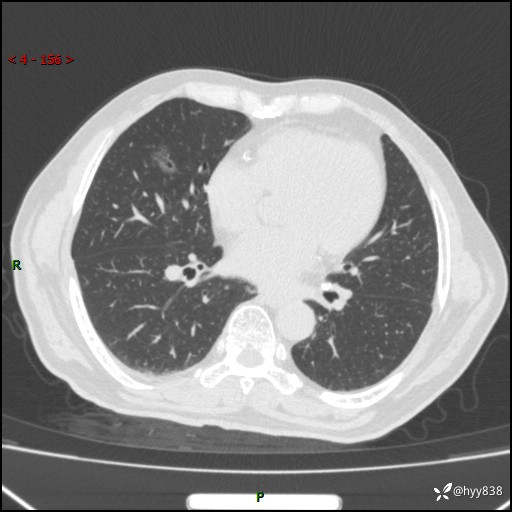

胸部CT平扫(2024.2)